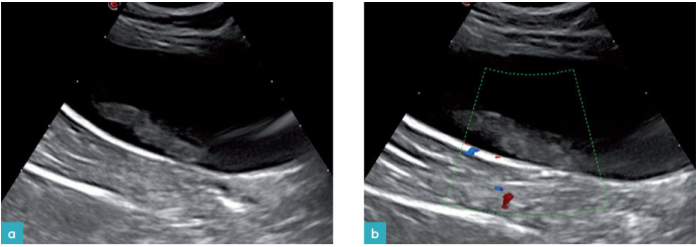

膀胱内的血凝块的回声通常是非均质结构,在膀胱腔内形成肿物。血凝块是没有彩色多普勒血流信号的,它可在膀胱内随体位的改变而移动。借此与肿瘤,附壁的炎症产物作以区分(图17-19)。

但是超声无法将膀胱出血,血肿与炎症,肿瘤做出区分(图20)。需要了解动物的病史以及跟踪检查评估病灶,才能做出正确的鉴别诊断(图20和21)。